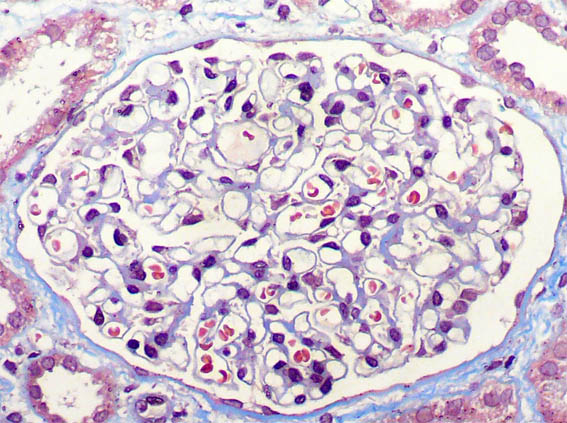

Figura 6.

Tricrómico de Masson, X400.